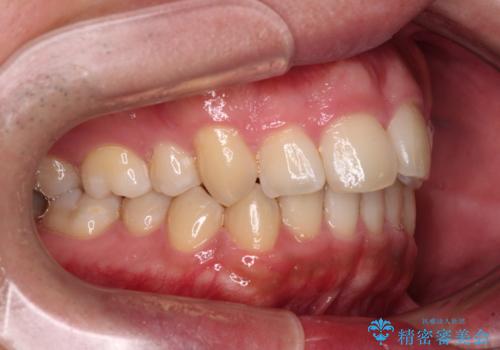

- 学生時代に抜歯矯正した歯列が後戻りしてきたとのことで来院された患者様です。

舌の突出癖が原因で上顎前歯が前方に移動したと考えられたため、舌のトレーニングを徹底して行っていただきながら、後戻りを解消していくこととしました。

マウスピース矯正でもワイヤー矯正でも対応可能でしたが、患者様の希望によりワイヤー装置による矯正治療を行うこととしました。

ワイヤー矯正ということで、上顎大臼歯を後方に移動するための補助装置を併用して、積極的に前歯を引っ込めていくこととしました。

上顎歯列全体がスムーズに後方移動でき、1年で治療を終えることができました。